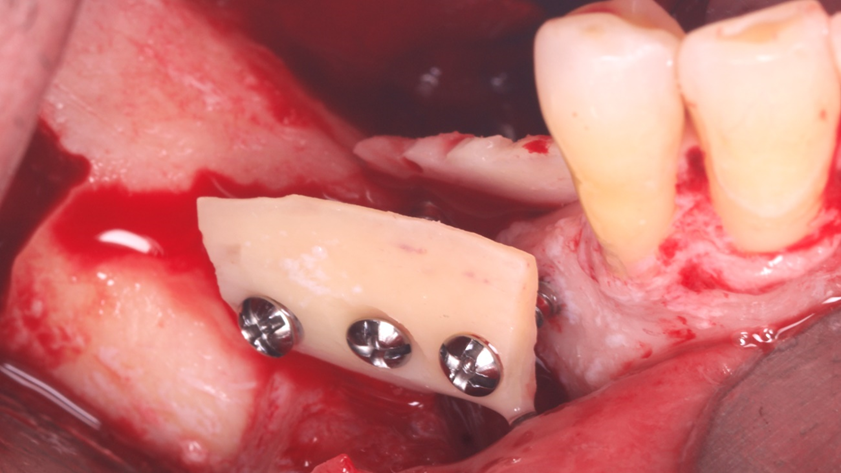

Homem de 60 anos foi encaminhado para reabilitação implantossuportada na região molar inferior direita (Figura 1). O volume ósseo remanescente tridimensional foi acessado por meio de tomografia computadorizada. Revelou uma deficiência vertical de modo que um aumento vertical foi planejado antes da colocação do implante. Seu histórico médico foi verificado e não foram encontradas comorbidades nem condições alérgicas. Não houve achados clínicos intraorais anormais, mas uma deficiência vertical na área molar inferior direita. Nenhum achado anormal foi perceptível no exame extraoral. Um enxerto autógeno em bloco ósseo dividido foi planejado para aumento horizontal e o ramo ipsilateral foi o local doador de escolha. A cirurgia foi realizada sob anestesia local com Articaína 4% e adrenalina 1:100.000. O paciente foi prescrito para enxaguar com Clorexidina 0,12% no pré-operatório, bem como tomar 1mg de Amoxicilina e 8mg de Dexametasona P.O. uma hora antes da cirurgia. Uma incisão mucoperiosteal foi realizada com bisturi número 15C desde o ramo mandibular até a borda mesiovestibular do primeiro pré-molar juntamente com uma incisão perpendicular obliquamente no vestíbulo mandibular. Após o descolamento da mucosa vestibular e liberação do nervo mentoniano, a mucosa lingual também foi descolada (Figura 2). Duas osteotomias verticais e uma horizontal foram realizadas no ramo mandibular com broca 701 para retirada do bloco ósseo necessário à reconstrução horizontal (Figura 3). Após a retirada do enxerto com auxílio de um elevador radicular, o bloco foi cortado longitudinalmente em dois pedaços finos com brocas discais e o osso esponjoso foi raspado para que pudesse ser utilizado como osso lascado (Figuras 4 a 8). Os blocos foram fixados na área edêntula. Um bloco foi fixado na face vestibular e o outro na face lingual. Cada um deles foi fixado com dois parafusos de osteossíntese de 1,5 mm e o osso lascado foi inserido no espaço entre eles (Figuras 9 e 10). A ferida foi fechada com fio de polipropileno 5-0, que foi retirado após 15 dias (Figura 11). A cirurgia cicatrizou sem intercorrências e o paciente recebeu prescrição de amoxicilina 500 mg P.O. a cada oito horas durante sete dias e ibuprofeno 600 mg a cada seis horas durante cinco dias.